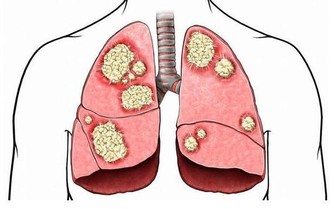

4、呼吸急促、喘不過氣,由於心臟沒有足夠血液能夠供血,

肺部缺氧所導致,這樣的情況若出現在新生兒上實,

尤其需要注意,這有可能是先天性的心臟病所造成。